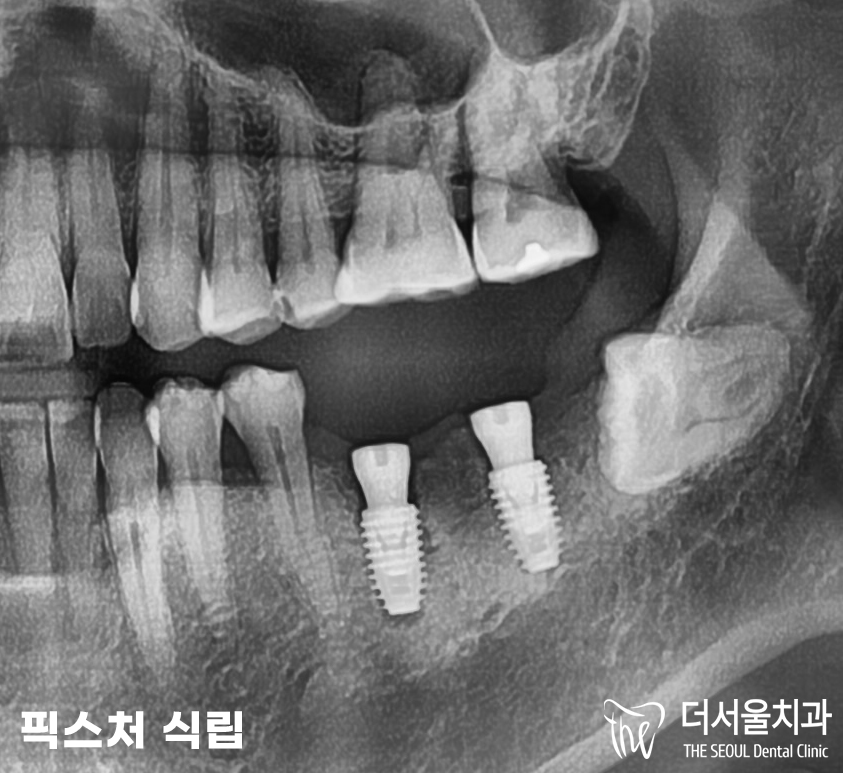

곧바로 모란역치과 의료진은

컴퓨터 분석 프로그램을 통해서

36, 37번 임플란트 식립 계획을

모의 수술로 확인했습니다.

아무래도 발치와 부분이 덜 회복되었으며,

잇몸뼈 상태가 그리 좋지 않았기에

미끄러짐이 발생할 가능성이 존재했습니다.

잘못하면 각이 틀어질 수 있기에

이 점을 조심해야 했죠.

또, 신경관과 긴밀한 거리였기에

좀 더 신중히 식립을 진행해 드려야 되었습니다.

골유도재생술(GBR)을 통하여

좀 더 뼈를 튼튼히

두께와 깊이감을 채울 수 있도록

만들어 놓은 뒤,

픽스처를 심기로 했습니다.

GBR로 뼈를 조금 더 튼튼히 만들어 준 뒤,

픽스처 식립을 진행했습니다.